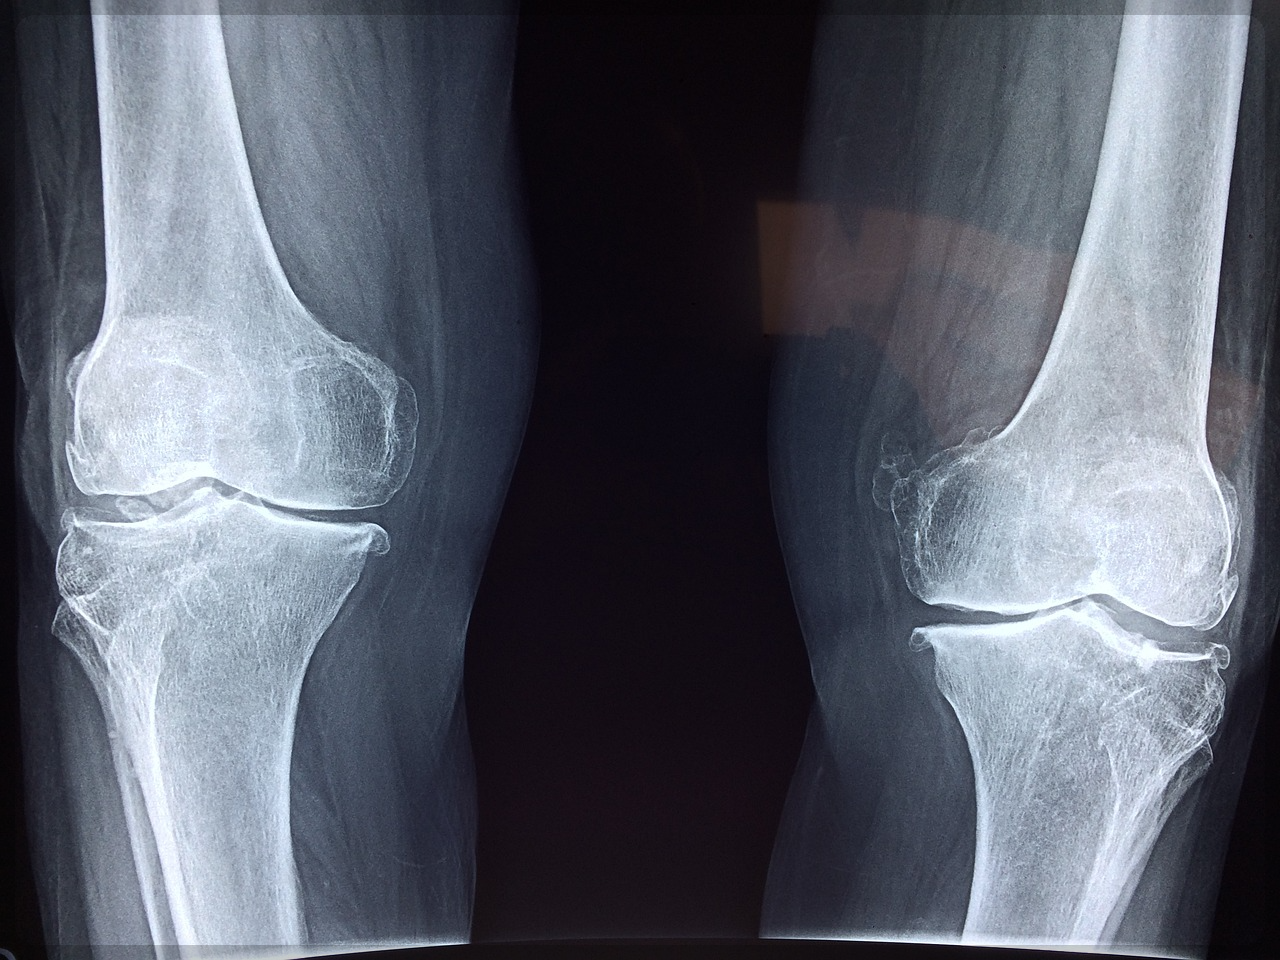

그런데 우리 몸의 연골을 파괴하는 강력한 위험인자가 있다는 사실 알고 계신가요?

그것은 바로 mmp라는 건데요.

이 mmp는 관절 조직 분해 효소로 관절 조직 및 구조 변화 관련 지표입니다.

나이가 들수록 mmp 발열이 과도해지면서 연골에 있는 콜라겐을 파괴하여 연골을 손상시키는 직접적인 원인으로 꼽히고 있습니다.

그런데 이 mmp의 계속되는 분비와 활성화로 연골은 완전히 붕괴되고 관절은 불안정해진다고 하는데요.

이렇듯 우리 건강에 치명적인 관절염을 개선하기 위해선 어떻게 해야 할까요?

결국 연골을 망가트리는 mmp와 같은 원인을 방지하고 연골을 최대한 건강하게 유지하는 게 관건이라고 볼 수 있습니다.